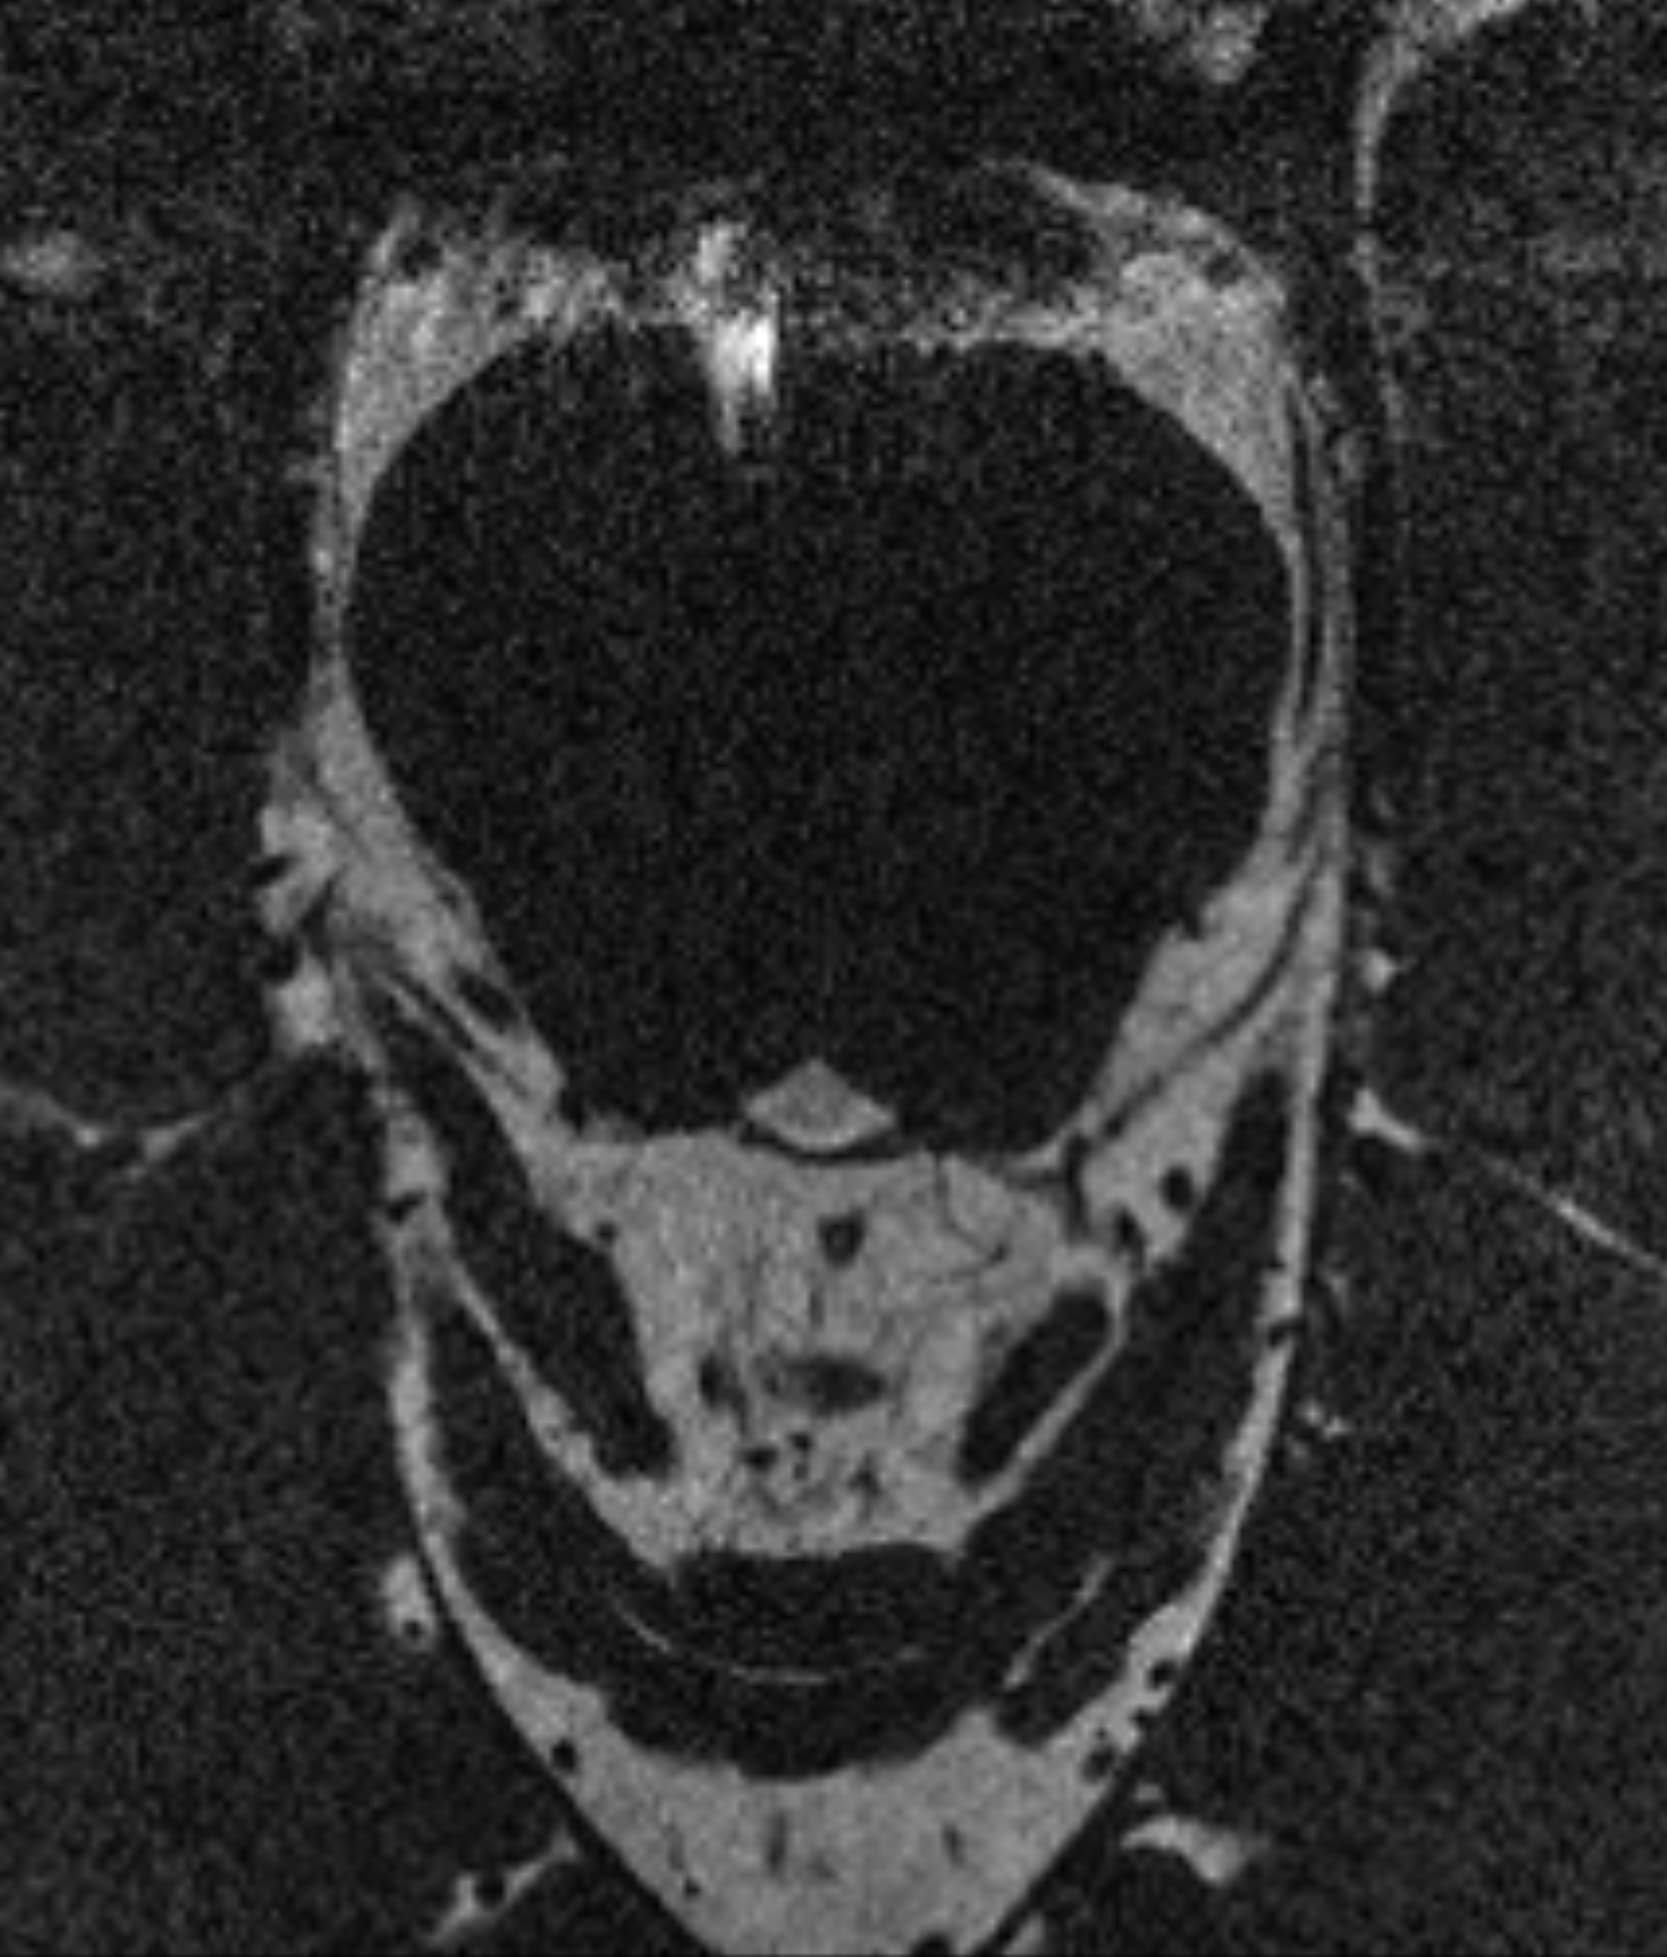

Δείτε πραγματικά παραδείγματα του SwiftMR™ σε διάφορα συστήματα MRI και ανατομικές περιοχές

Scan time 04:53

Scan time 1:46